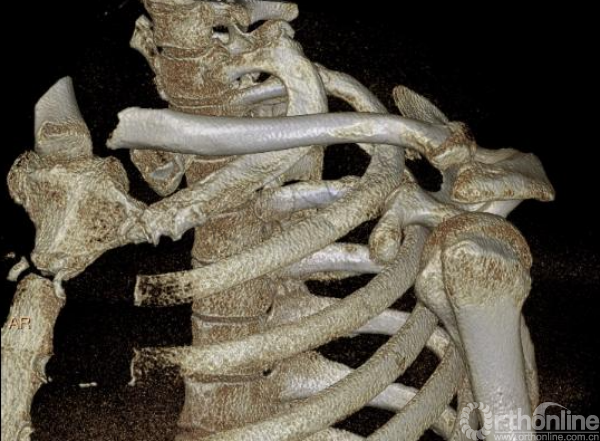

影像学检查—CT三维重建

1.创伤性漂浮锁骨(左侧)

(1)锁骨远端骨折

(2)锁骨近端骨折

(3)胸锁关节脱位

体位:仰卧位,患侧肩胛骨下放置软垫

治疗原则与术式选择

——坚强固定(近端-板钉)+弹性固定(远端-钩板)

(二)手术

入路与显露——胸锁关节

入路与显露——肩锁关节

复位与固定——肩锁关节(锁骨钩板)

术中透视

近端骨折脱位复位难、固定难(胸骨骨质特点),借用外科缝线复位捆扎方法达到满意疗效。

复位与固定——胸锁关节

复位与固定——胸锁关节(对侧锁骨远端解剖板塑形)

术后复查(肩关节正位及出口位)